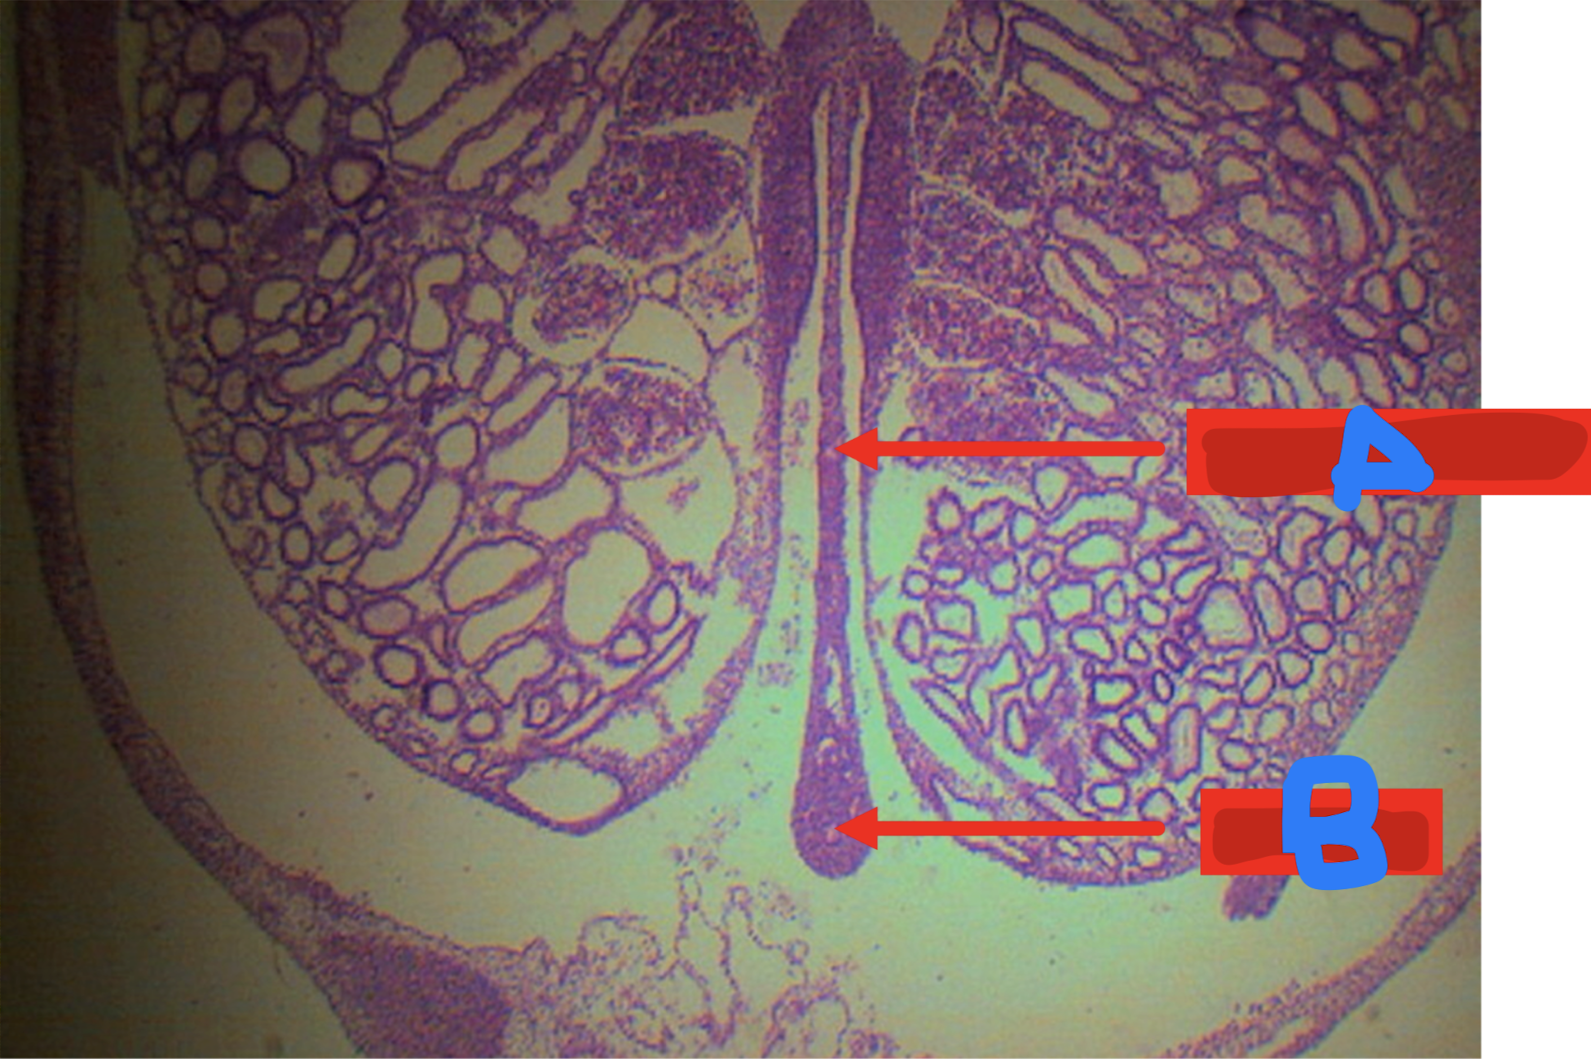

ILEUM

peyer’s patches

lymphoid nodular aggregates

Identify the structure and its characteristic feature

A: villi

B: peyer’s patch

C: submucosa

Identify the structure

A: muscularis mucosa

B: lamina propria

C: lining epithelium

D: peyer’s patch

E: crypts or lieberkuhn (intestinal glands)

F: submucosa